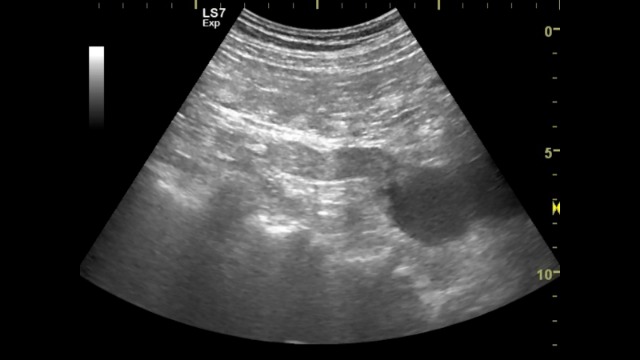

Пациент перенес несколько лет назад операцию по поводу рака толстой кишки.

Таир, наверно стоит переименовать ролик. Почему опухоль мочеточника? Скорее это сдавление мочеточника извне, предположительно регионарным метастазом.

Если я правильно поняла, мочеточник на протяжении заполнен гипоэхогенной солидной структурой, а кровоток при ЦДК интересно есть? именно заполнен, а не сдавлен... верно?

Мочеточник заполнен мочой на всем протяжении. В области интрамурального отдела (прилежит к стенке мочевого пузыря) какое то образование сдавливающее просвет мочеточника. Видно очень плохо.

Изображение сжимается на ютубе. Я обозначил на фото области поражения. Не затронут средний отдел. Из дистального и проксимального отделов навстречу идут два очага. При цистоскопии из устья видно образование.

видно как опухоль распространяется в лоханку